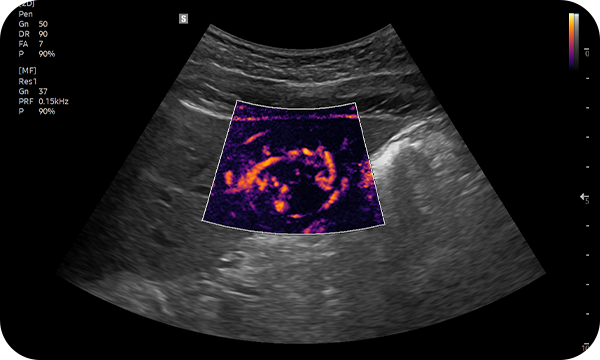

MV-Flow™ visualizes microcirculatory and slow blood flow to display the intensity in color. It is suitable for observation of microcirculatory and volume of slow blood flow.